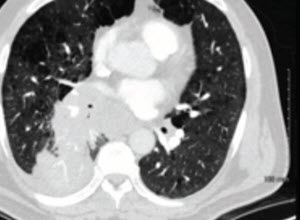

A 60-year-old woman with a large left hilar mass presented to the emergency room with worsening dyspnea. Advanced imaging demonstrated total occlusion of the left mainstem (LM) bronchus which was confirmed with direct visualization.